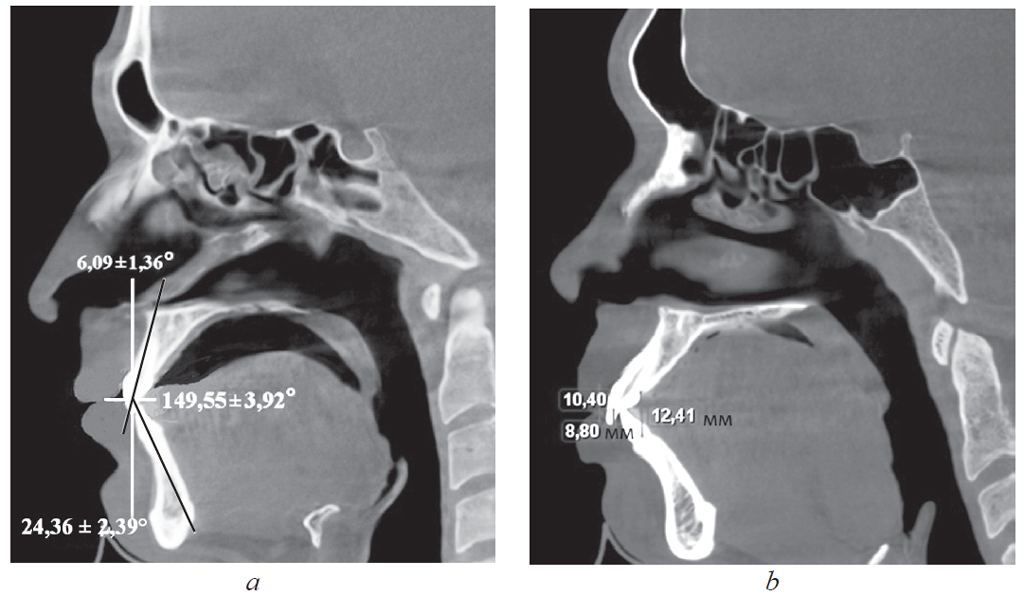

Результаты. У пациентов 1-й группы с протрузией резцов межрезцовый угол составил 149,55 ± 3,92°, торк верхних резцов — 24,36 ± 2,39°. При ретрузии резцов величина межрезцового угла составила 151,47 ± 2,94°, торк верхних резцов — 5,85 ± 1,42°. При этом величина вертикального перекрытия соответствовала величине сагиттального перекрытия и не превышала 2–3 мм. У пациентов 2-й группы, как правило, отмечалось нарушение формы зубных дуг в переднем отделе.

У людей 1-й подгруппы, для которых было характерно протрузионное положение резцов, межрезцовый угол составил 117,24 ± 2,85°. При этом торковые значения верхних резцов по отношению к окклюзионной плоскости составили 12,24 ± 2,48° (рис. 2).

Рис. 2. Физиологическая протрузия резцов на томограммах

Fig. 2. Physiological protrusion of incisors on tomograms

Достоверных отличий при измерении величины перекрытия в сагиттальном и вертикальном направлениях нами не отмечено.

У людей 2-й подгруппы при ретрузии резцов величина межрезцового угла в среднем составила 151,47 ± 2,94°, торк верхних резцов — 5,85 ± 1,42°. При этом величина вертикального перекрытия соответствовала величине сагиттального перекрытия и не превышала 2–3 мм.

У людей 1-й подгруппы, для которых было характерно протрузионное положение резцов, межрезцовый угол составил 117,24 ± 2,85°, при этом торковые значения верхних резцов по отношению к окклюзионной плоскости — 12,24 ± 2,48° (рис. 4).